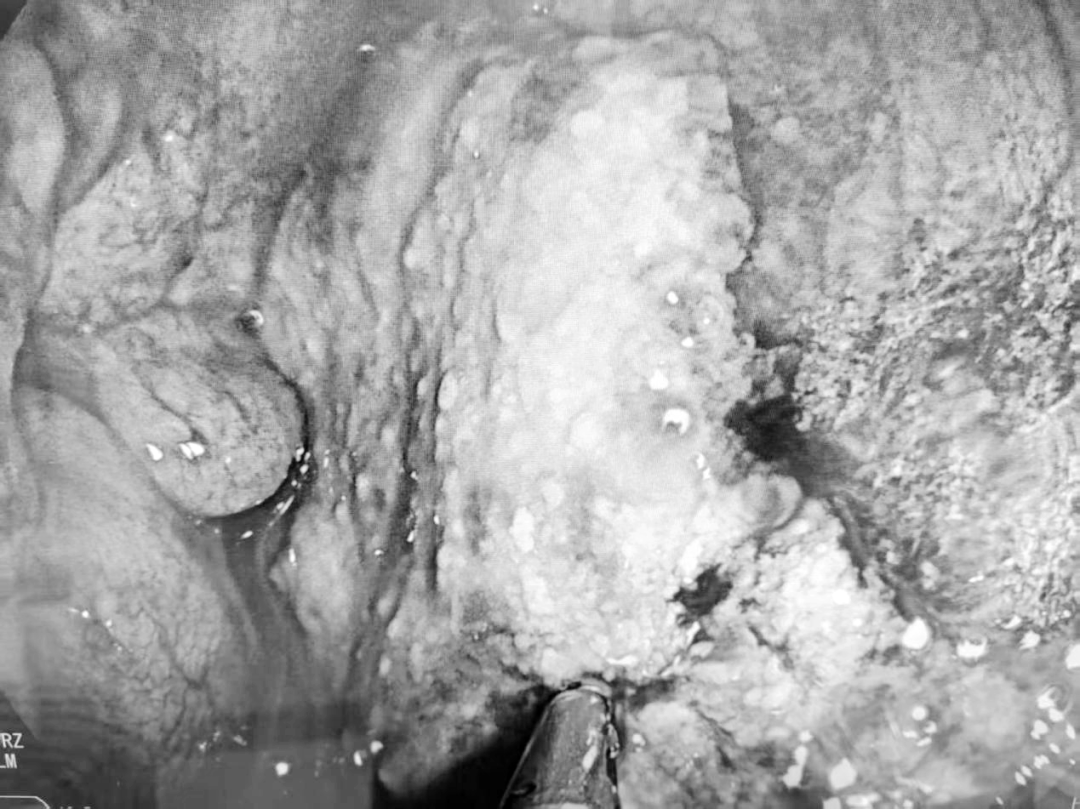

手术中,专家团队通过患者脐部这一天然褶皱处建立微小通道,将胃镜灵活引入腹腔。在清晰的內镜视野下,团队对腹腔进行了系统、全面的探查。最终,在腹腔内发现了腹膜病灶,并成功实施了精准活检。术后病理回报确诊为“高级别浆液性癌”。这一关键诊断,一举揭开了肿瘤来源的迷雾,为后续精准治疗指明方向。